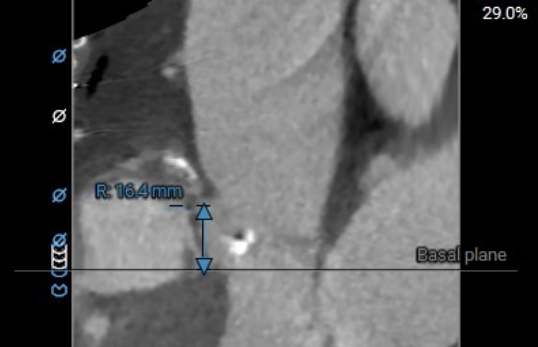

右冠高度:16.4mm

右冠高度:13.7mm

术前主动脉CTA评估:主动脉瓣二叶式type1型,L-R融合,瓣叶增厚、黏连,瓣叶游离缘、根部及融合脊中-重度钙化;主动脉瓣环周长折算直径约25.2mm;双侧冠脉开口高度可;双冠分支轻度钙化;术中建议造影角度LAO:9°,CRA:11°;左室流出道稍凸出;主动脉弓及降主动脉多发钙化,腹主动脉重度钙化。

术前主动脉CTA评估:主动脉瓣三叶式,瓣叶基本等大,瓣叶增厚、黏连,瓣叶游离缘中-重度钙化,左-无、右-无交界钙化融合。主动脉瓣环周长折算直径约28.6mm;左侧冠脉开口高度稍低LCA:9.6mm,RCA:13.7mm;右冠及左冠分支轻度钙化;左室流出道轻度钙化。升主动脉增宽;双侧髂外动脉迂曲,余未见明显迂曲。